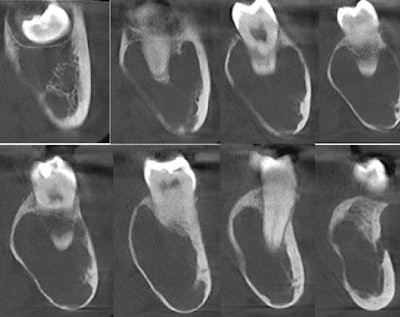

The oral surgeon ordered a cone-beam computed tomography (CBCT) scan. Below are the following images:

- CBCT coronal images of the left posterior mandible

Figure 2: CBCT coronal images of the left posterior mandible.

There is a large hypodense lesion (radiolucent), well defined and corticated, extending from the mesial aspect of tooth #17 to the periapical area of tooth #22. The lesion goes from the inferior cortex of the mandible to the alveolar ridge of teeth #18 and #19, the middle third of the root of tooth #20, and the apical third of the root of tooth #21. There is evidence of significant expansion in the coronal and axial projections. No calcifications are observed within the lesion. No periosteal reaction is observed (lingual or buccal). There is no radiographic evidence of perforation of the buccal or lingual walls of the lesion.

There is no radiographic evidence of root resorption or teeth displacement associated with the lesion. No gross caries is present in the teeth involved in the lesion. The inferior alveolar canal is well visualized and displaced buccally-apically by the lesion.

From the radiographic perspective, unicystic ameloblastomas show expansive unilocular radiolucency with well-defined and well-corticated borders. Root resorption is often present with minimal displacement. The majority of cases are associated with an impacted or unerupted tooth. The differential diagnosis includes dentigerous cyst and keratocystic odontogenic tumor.